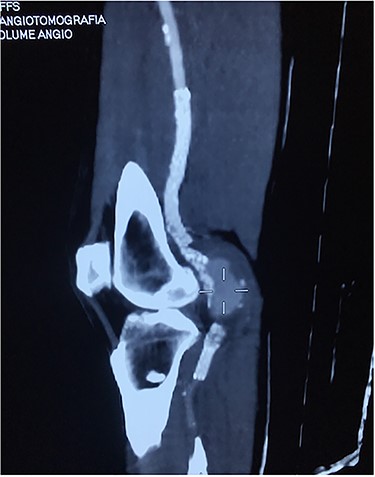

Approval for retrospective reports is not required by our institutional review board. This study is in accordance with the principles of the Declaration of Helsinki. A 77-year-old man with multiple comorbidities, including coronary vascular disease, hypertension, dyslipidemia, previous right carotid endarterectomy, and endovascular aortic repair (in 2011), was referred to our unit for evaluation of a retropopliteal pulsatile mass. He had undergone infra-popliteal stenting 18 months earlier, to treat peripheral arterial disease with severe left claudication. The procedure was performed at another vascular institute, and the stent type was unknown. Physical examination revealed the presence of a femoral and popliteal pulse and the absence of tibial pulses; at admission, the ankle–brachial index was 0.8. According to the patient, he had noticed the mass in the last 2 months prior to admission, but the absence of pain delayed his presentation to the hospital. An ultrasound scan was performed on admission and revealed a large popliteal pseudoaneurysm with normal flow present distally, and fracture of the stent was confirmed by computed tomography, which also detected a 4.2 cm dilatation of the left popliteal artery (Figs 1–3).

Angiotomography of the popliteal region highlighted the complete stent fracture and a large pseudoaneurysm formation.